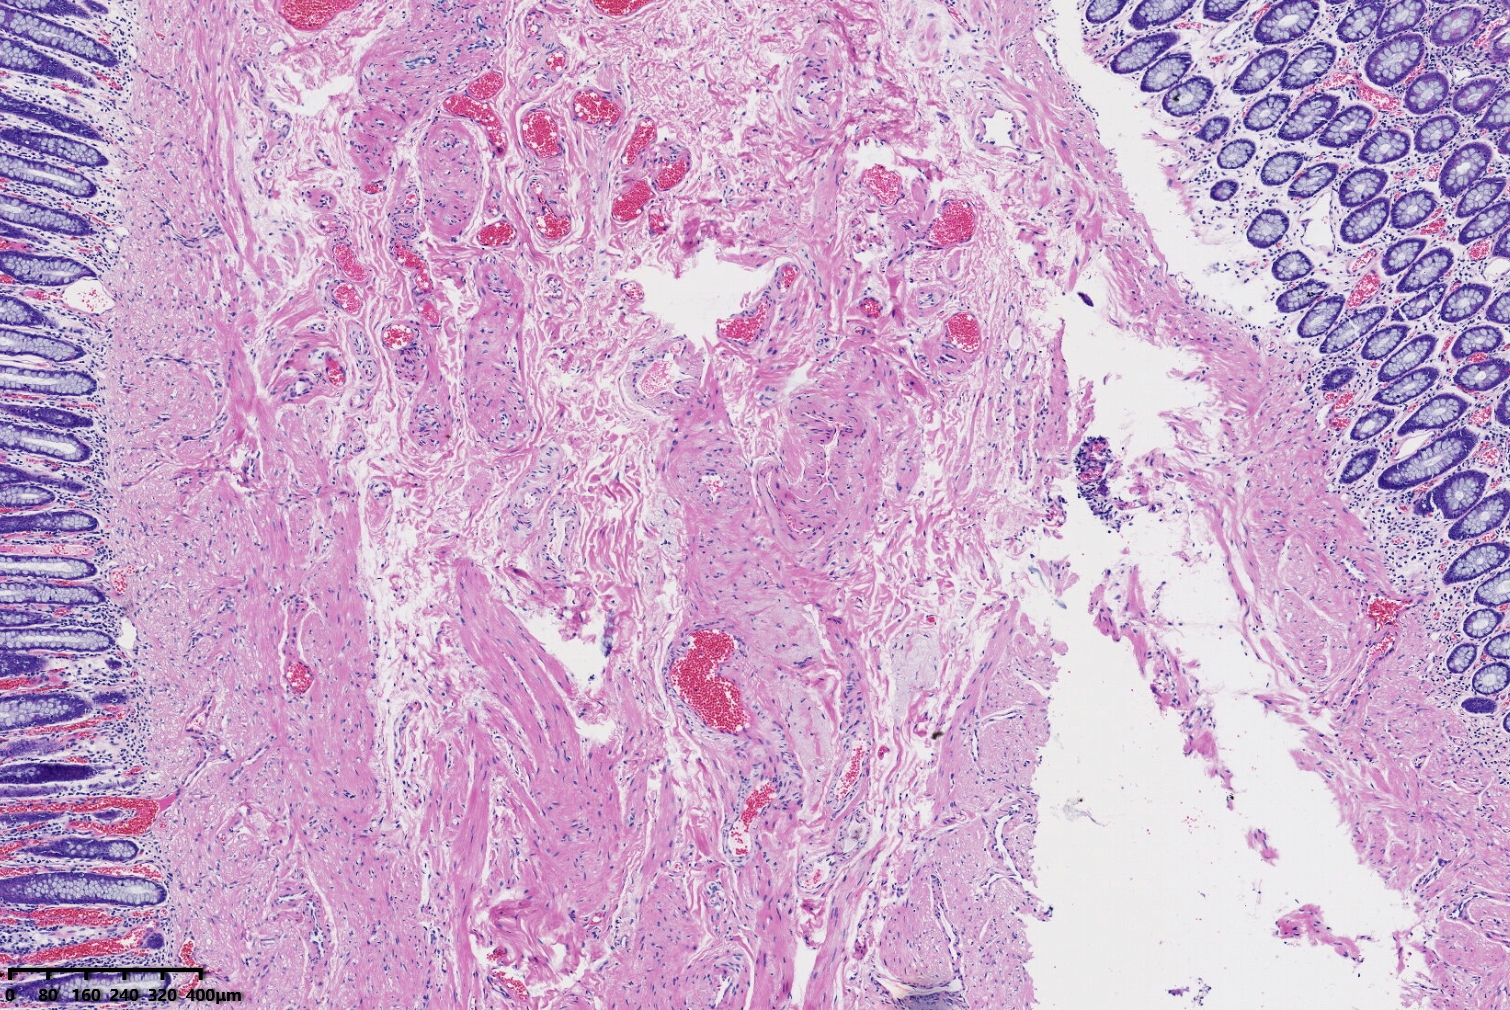

结肠息肉,请教老师们发什么息肉妥当?

结肠息肉

炎性息肉(黏膜脱垂相关息肉)

形态符合粘膜脱垂相关息肉。